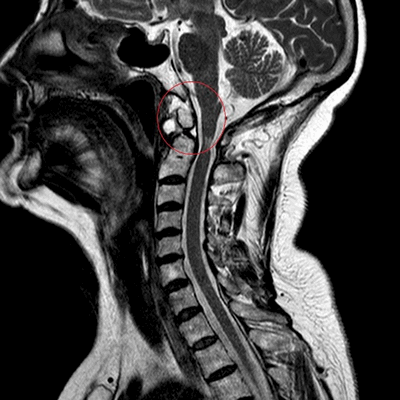

Опухоль (предположительно менингиома) на МРТ шейного отдела позвоночника